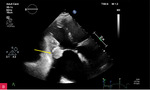

Rycina 4A, B. Badanie echokardiograficzne przezklatkowe trójwymiarowe (3D TTE) – widok od strony lewej komory zastawki mitralnej i guzowatej zmiany o nierównej powierzchni (A) wraz z prezentacją zmiany w przekrojach wykonanych na podstawie 3D TTE (B)

Rycina 5A-C. Badanie echokardiograficzne przezklatkowe dwuwymiarowe (2D TTE) w projekcji koniuszkowej czterojamowej. Znacznie powiększone przedsionki i niewielkie wymiary komór serca. W zależności od płaszczyzny przekroju w kierunku przód–tył (A, B, C) zmienia się uwidocznienie zmiany guzowatej – CCMA (serowate zwapnienie pierścienia mitralnego). Jest ona w pełni widoczna w zmodyfikowanej projekcji obrazującej struktury położone jak najdalej ku tyłowi serca (C)